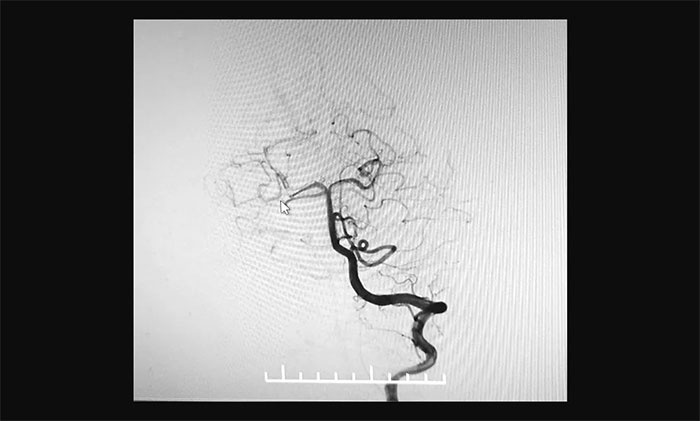

最終,在麻醉科團(tuán)隊(duì)及導(dǎo)管室介入團(tuán)隊(duì)的密切配合和監(jiān)護(hù)下,神經(jīng)外科于耀宇主任團(tuán)隊(duì)歷時(shí)2小時(shí),為王女士順利實(shí)施腦血管造影+顱內(nèi)動(dòng)脈瘤栓塞術(shù)。術(shù)中,DSA造影確診右側(cè)小腦上動(dòng)脈夾層動(dòng)脈瘤,動(dòng)脈瘤瘤體大小約為4x3 mm。術(shù)中,于耀宇主任憑借嫻熟的技術(shù),克服血管迂曲等困難,將栓塞導(dǎo)管成功送入夾層動(dòng)脈瘤內(nèi),最終順利栓塞夾層動(dòng)脈瘤。術(shù)后,再次造影未見動(dòng)脈瘤顯影,見遠(yuǎn)端分支顯影良好,“炸彈”危險(xiǎn)被成功解除。術(shù)后,患者順利蘇醒,無神經(jīng)功能障礙。

▲ 栓塞后